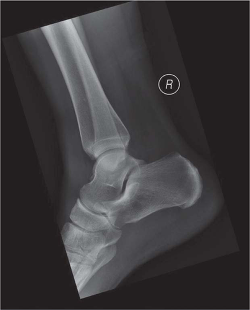

Radiographic evaluation included anteroposterior, lateral, and mortise with a gravity stress view of the ankle. This revealed an anterior process fracture of the calcaneus (see Figure 1) as well as widening of the medial clear space, consistent with ligamentous injury (see Figure 2). Given this, as well as noted ligamentous laxity on examination, a magnetic resonance imaging (MRI) of the ankle was obtained. The MRI revealed the known anterior process fracture without significant displacement, bone contusions throughout the midfoot, split tear of the peroneus brevis, and partial tear of the anterior talofibular ligament. These associated soft tissue findings are commonly reported with anterior process fractures (Ouellette, Salamipour, Thomas, & Kassarijian, 2013).

Figure 1 - Click to enlarge in new windowFigure 1. Note fracture of the anterior process of calcaneus, minimally displaced.